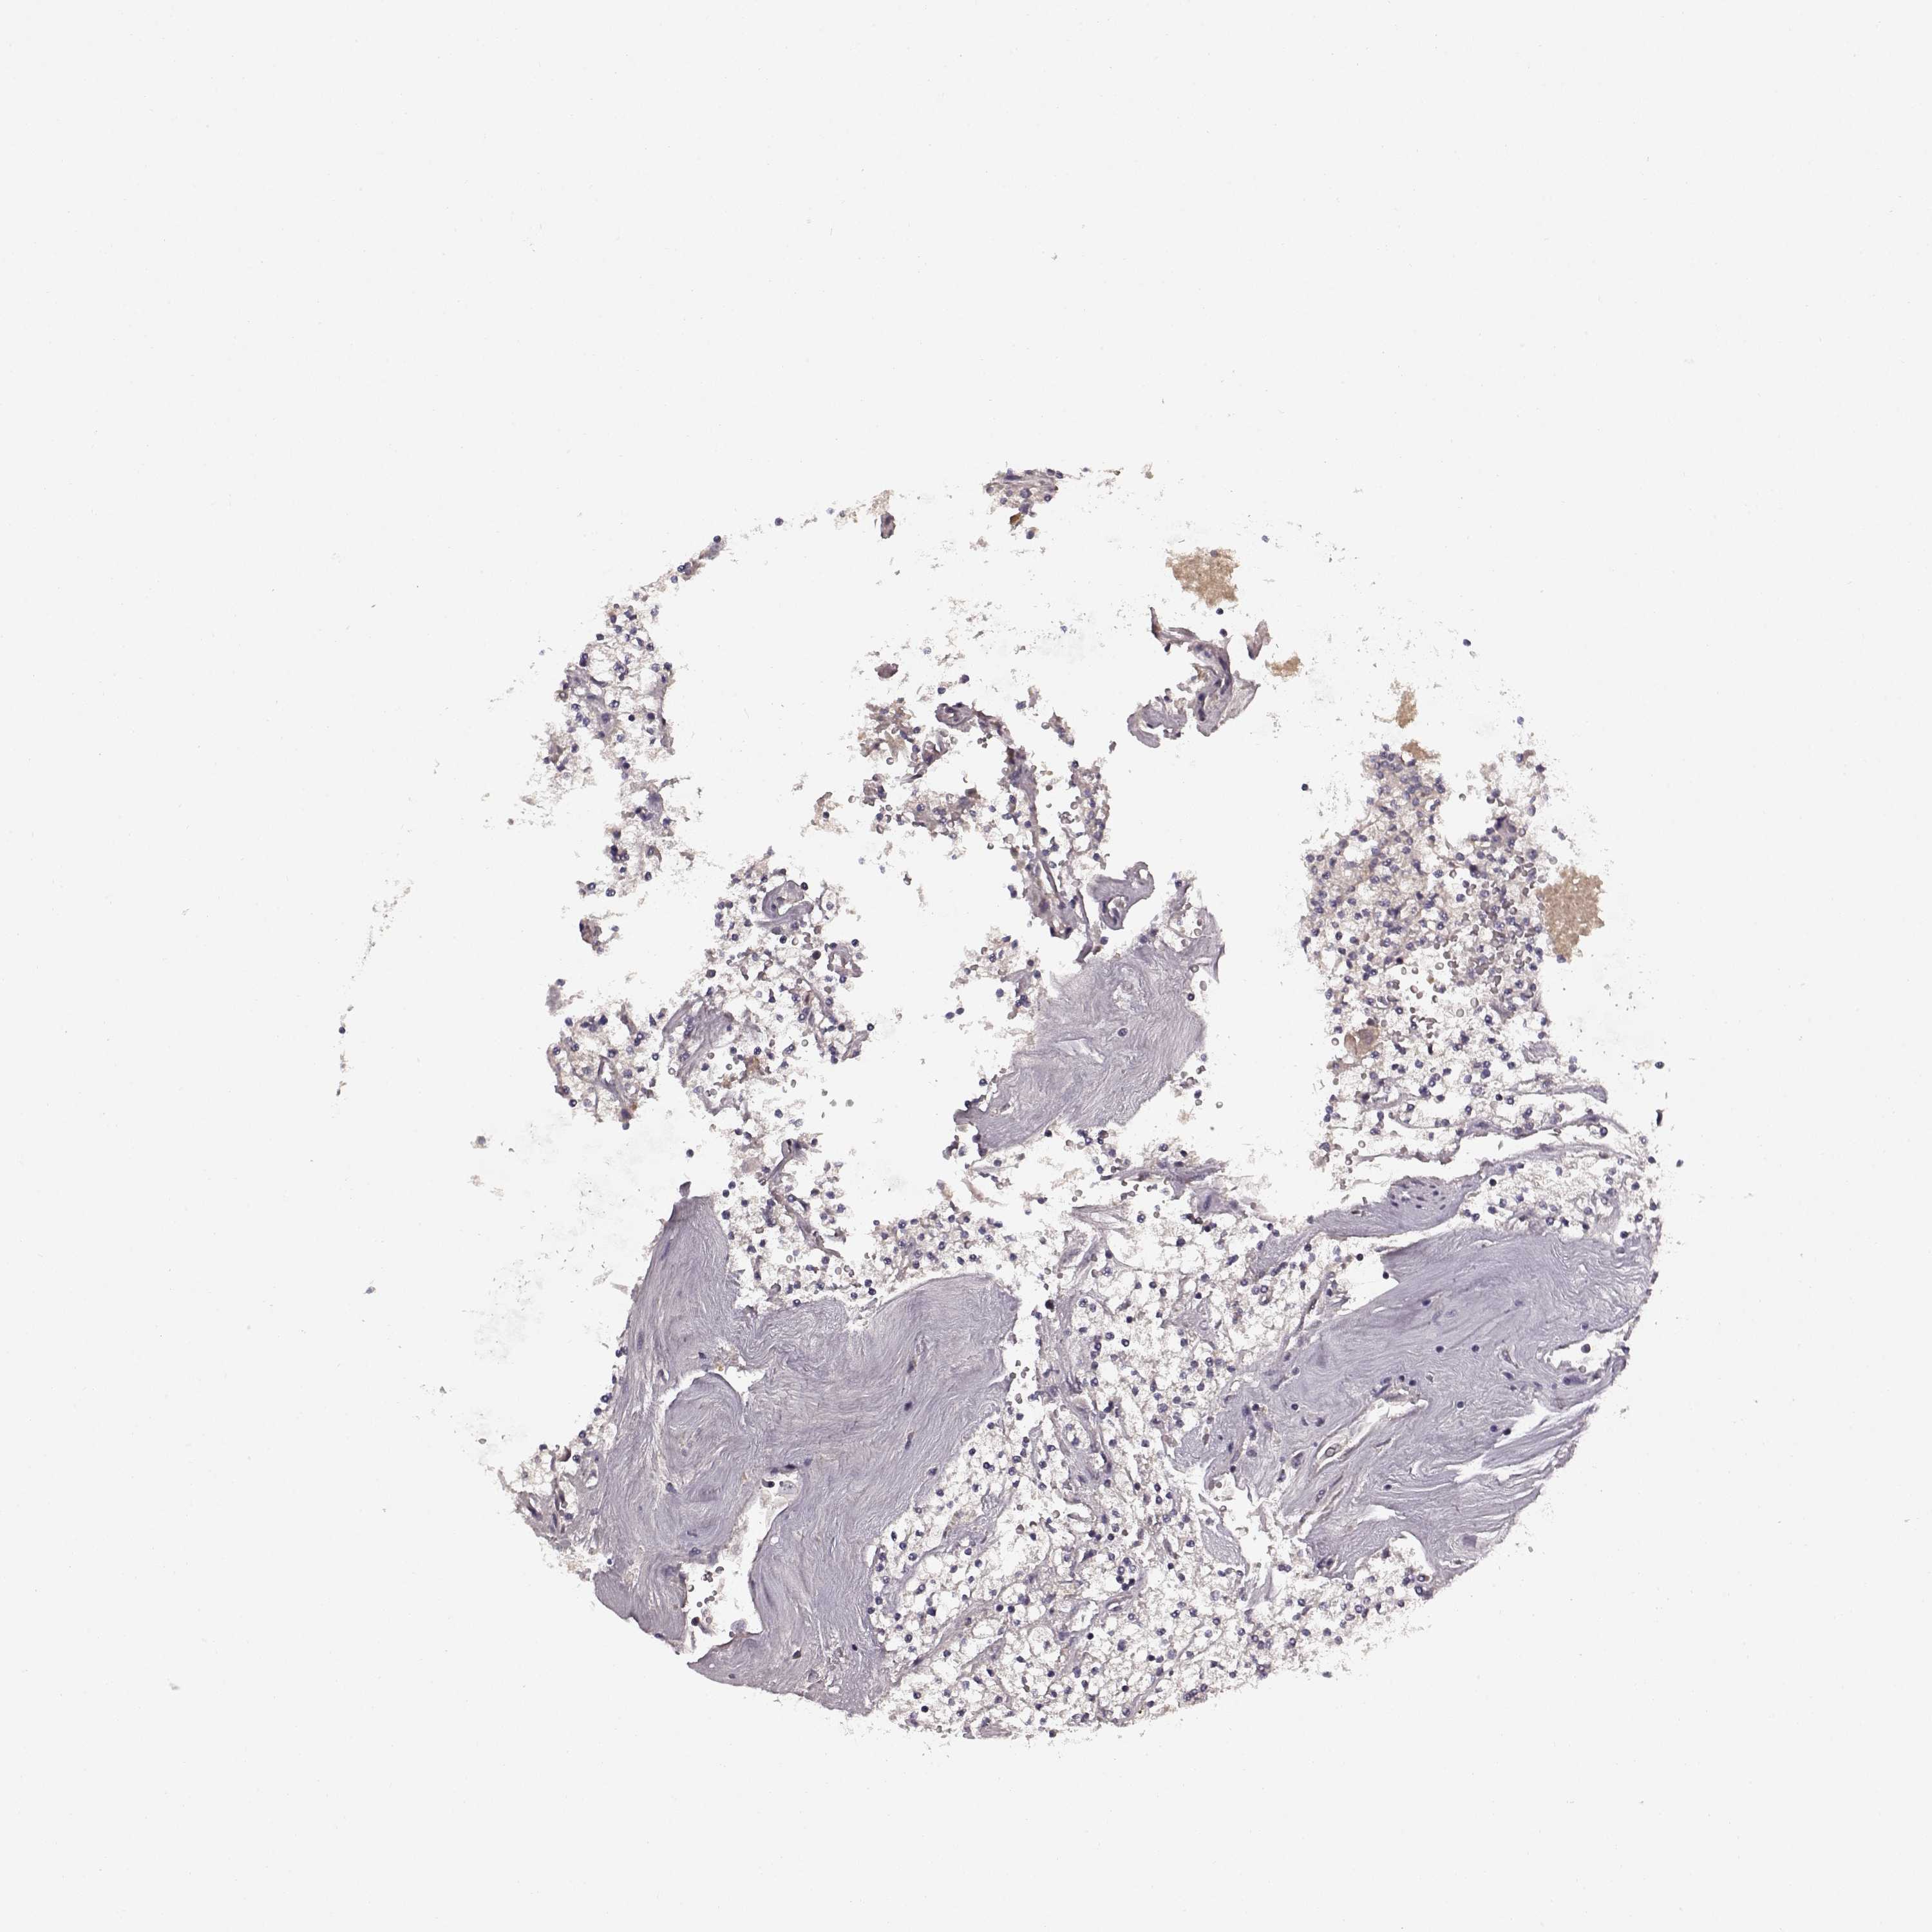

KICH TCGA KIRC TCGA KIRC VALIDATION KIRP TCGA PROTEIN RCC CPTAC PROTEIN EXPRESSION

Renal cancer

Kidney renal clear cell carcinoma

KIDNEY RENAL CLEAR CELL CARCINOMA (VALIDATION) - Interactive survival scatter ploti

SLC22A18 is not prognostic in Kidney Renal Clear Cell Carcinoma (validation)

Average pTPM 20.0

Number of samples 100